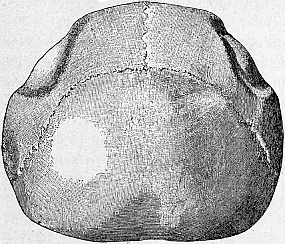

Sehen wir uns die inneren Organe eines alten Menschen an, so finden wir, daß sie kleiner sind als bei einem jüngeren Menschen. Man kann direkt von einem Schwund der Organe im Alter sprechen. Wir haben schon des äußerlich sichtbaren Schwundes vom Unterkiefer gedacht. Auch die Knochen sonst erleiden einen richtigen Schwund, die Schädelknochen (Abb. 16) und alle andern auch. Die Knochen werden dünner, und die Verdünnung der Knochen geht so weit, daß sie brüchig werden. Jedermann weiß, daß alte Leute leicht Knochenbrüche[38] erleiden, namentlich an bestimmten Knochen, z. B. am Schenkelhals. Und wie die Knochen, so erfahren auch alle andern Organe im Alter einen Schwund: die Leber, die um die Hälfte verkleinert sein kann, die Nieren, das Herz usw. Besonders auffallend aber ist der Schwund, den das Gehirn bei alten Leuten erfährt. Die Windungen des Gehirnes, die aus Nervenzellen bestehen, sind schmäler geworden, weit klaffen die Furchen zwischen den Windungen. Aber nicht nur kleiner, auch härter sind die Organe im Alter geworden. Derb und zähe fühlt sie der Arzt in der Hand, wenn er die Leichenschau übt.

Abb. 16. Schädeldach eines alten Menschen. Rechts und links an den Scheitelknochen sieht man sehr deutlich den Knochenschwund: es sind hier flache Gruben im Knochen entstanden. Nach Ziegler.